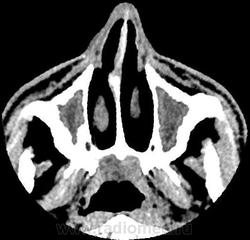

- тотальное снижение пневматизации обоих половин лобных пазух, обоих гайморовых пазух, передней и средней групп ячеек решетчатого лабиринта с двух сторон патологическим содержимым плотностью +17+23HU. Устья гайморовых пазух блокированы патологическим субстратом.

-определяются костные дефекты задней стеки правой половины лобной пазухи, определяется дефект перегородки, разделяющей половины лобной пазухи, дефект передней части костной стенки левой половины лобной пазухи. Дефект верхне-медиального отдела крыши правой орбиты.

Также определяется канал со склеротическим контуром, сообщающийся с полостью левой гайморовой пазухи и полостью рта, шириной 1,7 мм являющийся ороантральным свищом;

-признаки хронического остемиелита в виде неравномерного утолщения костных стенок (гиперостоз) обоих гайморовых пазух, обоих половин лобной пазухи, истончение и изъеденность стенок средней группы ячеек решетчатого лабиринта справа, изъеденность медиальной стенки орбиты (бумажная пластинка решетчатой кости) справа. Патологических изменений со стороны ретробульбарной клетчатки, содержимого орбиты достоверно не выявлено.

Заключение: КТ признаки полисинусита, осложненного хроническим остеомиелитом стенок гайморовых и обоих половин лобной пазухи, ячеек решетчатого лабиринта справа, наличием участков деструкции стенок обоих половин лобной пазухи, зоны энцефалита в полюсно-базальных отделах правой лобной доли. Полипы передне-верхней стенки левой половины основной пазухи, среднего носового хода справа. Признаки ороантрального свища слева.